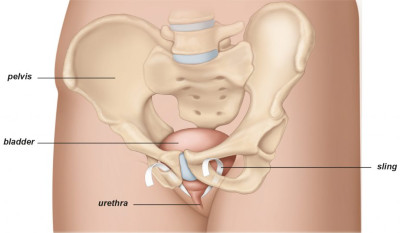

Είναι το συχνότερο είδος ακράτειας στις γυναίκες και οφείλεται στην χαλάρωση του πυελικού εδάφους (Εικ.1) αλλά και στην εμμηνόπαυση.

Εικ.1: Το γυναικείο Πυελικό Έδαφος